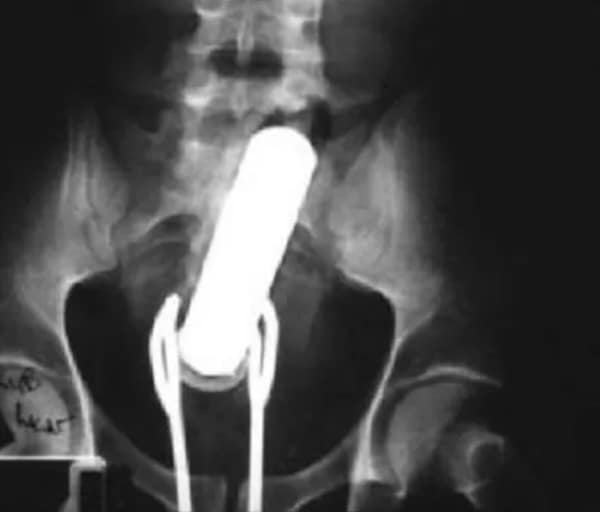

I used to think that nothing could surprise me anymore—until I stumbled upon some weird x-ray photos that made me reconsider my stance on human ingenuity (or lack thereof). Apparently, some people have a knack for getting objects lodged where they absolutely shouldn’t be. If you’ve ever wondered how not to use everyday items, these images might provide some unintended guidance.

This collection showcases 31 bizarre x-ray images that defy logic and anatomy textbooks alike. Each photo reveals unexpected objects making cameo appearances inside the human body, turning medical imaging into a gallery of the absurd. From common household items inexplicably found in unusual places to anomalies that would leave even seasoned doctors scratching their heads, these images offer a perplexing glimpse into the more “creative” side of medical emergencies. They highlight the intersection of curiosity, misadventure, and perhaps a dash of poor decision-making, all captured through the lens of radiology.